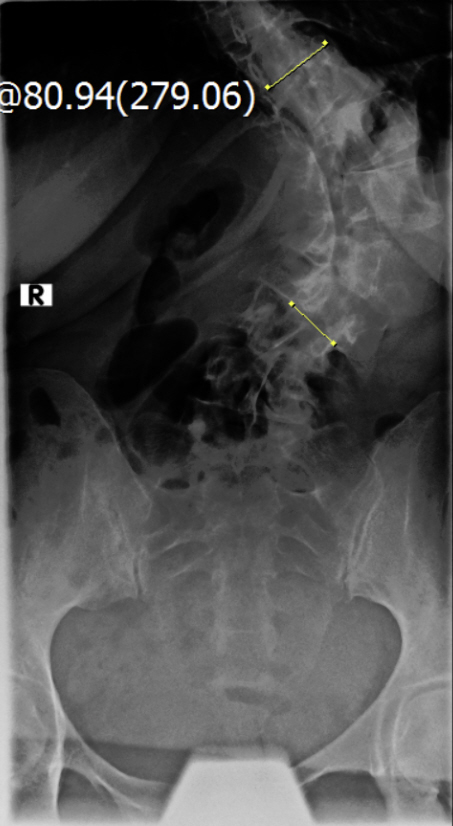

Thorakolumbalskoliose mit aktuellen COBB-Winkeln von 80 und 60 Grad...wenig Schmerzen und daher meistens glücklich

Viele kennen sich aus, daher möchte ich euch meine aktuellen Röntgenbilder nicht vorenthalten und hänge sie unten an.

Ich war beim MVZ Gersthofen, dort wurden die Röntgenbilder gemacht…die massive Verschlechterung war sehr offensichtlich

Dort wurden die Winkel gemessen, unten 80 Grad und oben 60 Grad…eine Verschlechterung von über 2 Grad pro Jahr, wenn man es auf die ganze Zeit berechnet

Die Winkel hab ich nachgemessen, wie der Arzt der Hessing und hier mal als Screenshot